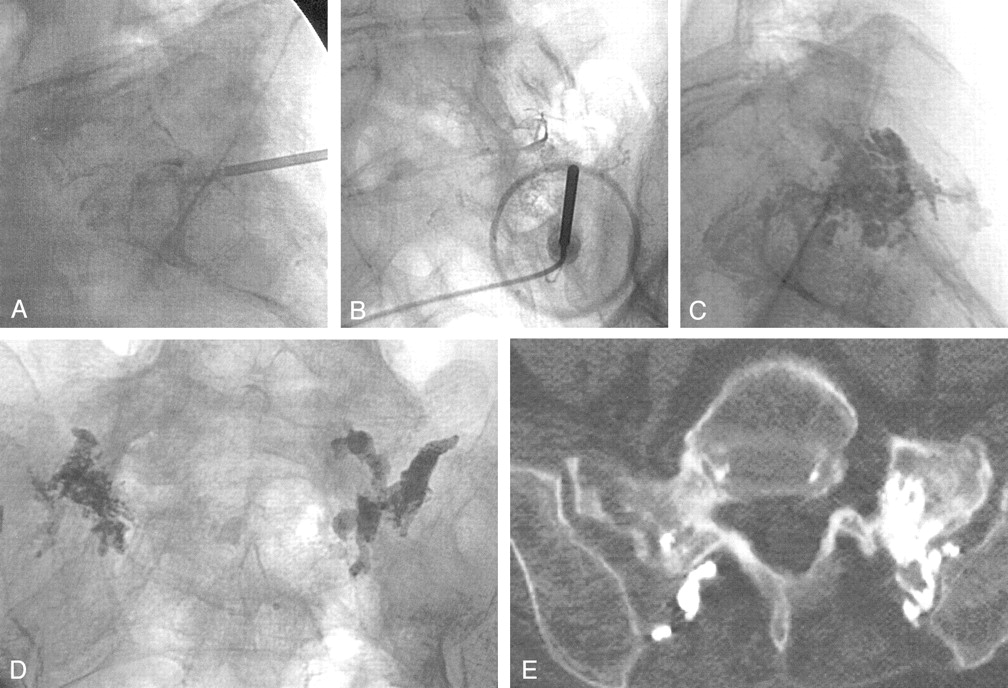

A 71-year-old woman had recurrent sudden-onset lower back pain that she rated 10 out of 10 for several months since falling. This acute pain differed from her chronic lower back pain. She relied on a walker for mobility. MR imaging and bone scintigraphy performed at another institution showed an old T11 compression fracture and bilateral sacral insufficiency fractures. Vertebroplasty at T11 was performed first, although her pain distribution was more clearly related to the sacral area. The subsequent sacroplasty was similar to that performed in our first patient, although venography was attempted for assessing needle placement (Fig 2A and B). Again, visualization of cement within the sacrum was difficult by fluoroscopy alone, and, in retrospect, the volume of cement in each of these first two cases (2–6 mL) was conservative because of increasing operator uncertainty regarding needle location (Fig 2C and D). A postoperative pelvic CT scan showed cement within the left sacrum, but the right sacral injection resulted in a portion of the cement being positioned within the posterior soft tissue (Fig 2E). Pain relief was immediately apparent by the time of discharge, later that same day, and was sustained through her 1-month follow-up clinic visit. She discontinued her pain medications. Her general activities of daily living were much improved and were described to be back to baseline by herself and her family members. In telephone follow-up with the patient 14 weeks after the procedure, she reported she was “wonderfully improved” and pain free in her lower back.

Case 2, a 71-year-old woman with sacral insufficiency fracture.

A and B, Anteroposterior (A) and lateral (B) venograms do not clearly confirm needle tip placement within the sacrum. Again, notice the difficulty in confirming the needle tip location as being entirely intraosseous.

C and D, Anteroposterior (C) and lateral (D) fluoroscopic images show cement within the sacrum.

E, Postoperative pelvic CT scan shows cement within the left sacrum, but the right sacral injection has resulted in a portion of the cement being positioned within the posterior soft tissue